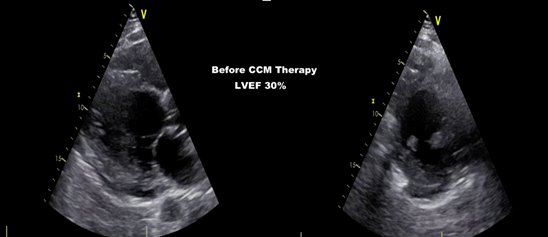

In 2020, the same patient was admitted to the emergency department with pleural effusion and pedal edema, and breathing difficulty for several days. Echocardiographically severe left ventricular dysfunction (LVEF 30%)(Figure 2), the blood investigation showed further deranged kidney function, and high Nt Pro BNP (14000 pg/ml). Vital parameters like Blood pressure of 92/60mm Hg, Herat rate of 70/min, and CRT Interrogation showed 99% biventricular stimulation. Considering the whole clinical parameter and CRT Function, it was diagnosed as CRT- Nonresponder. Because of low Blood pressure and deranged kidney function further optimization of guideline-directed medical therapy was not possible.

Figure 2Echocardiography before CCM Therapy, LVEF 30%